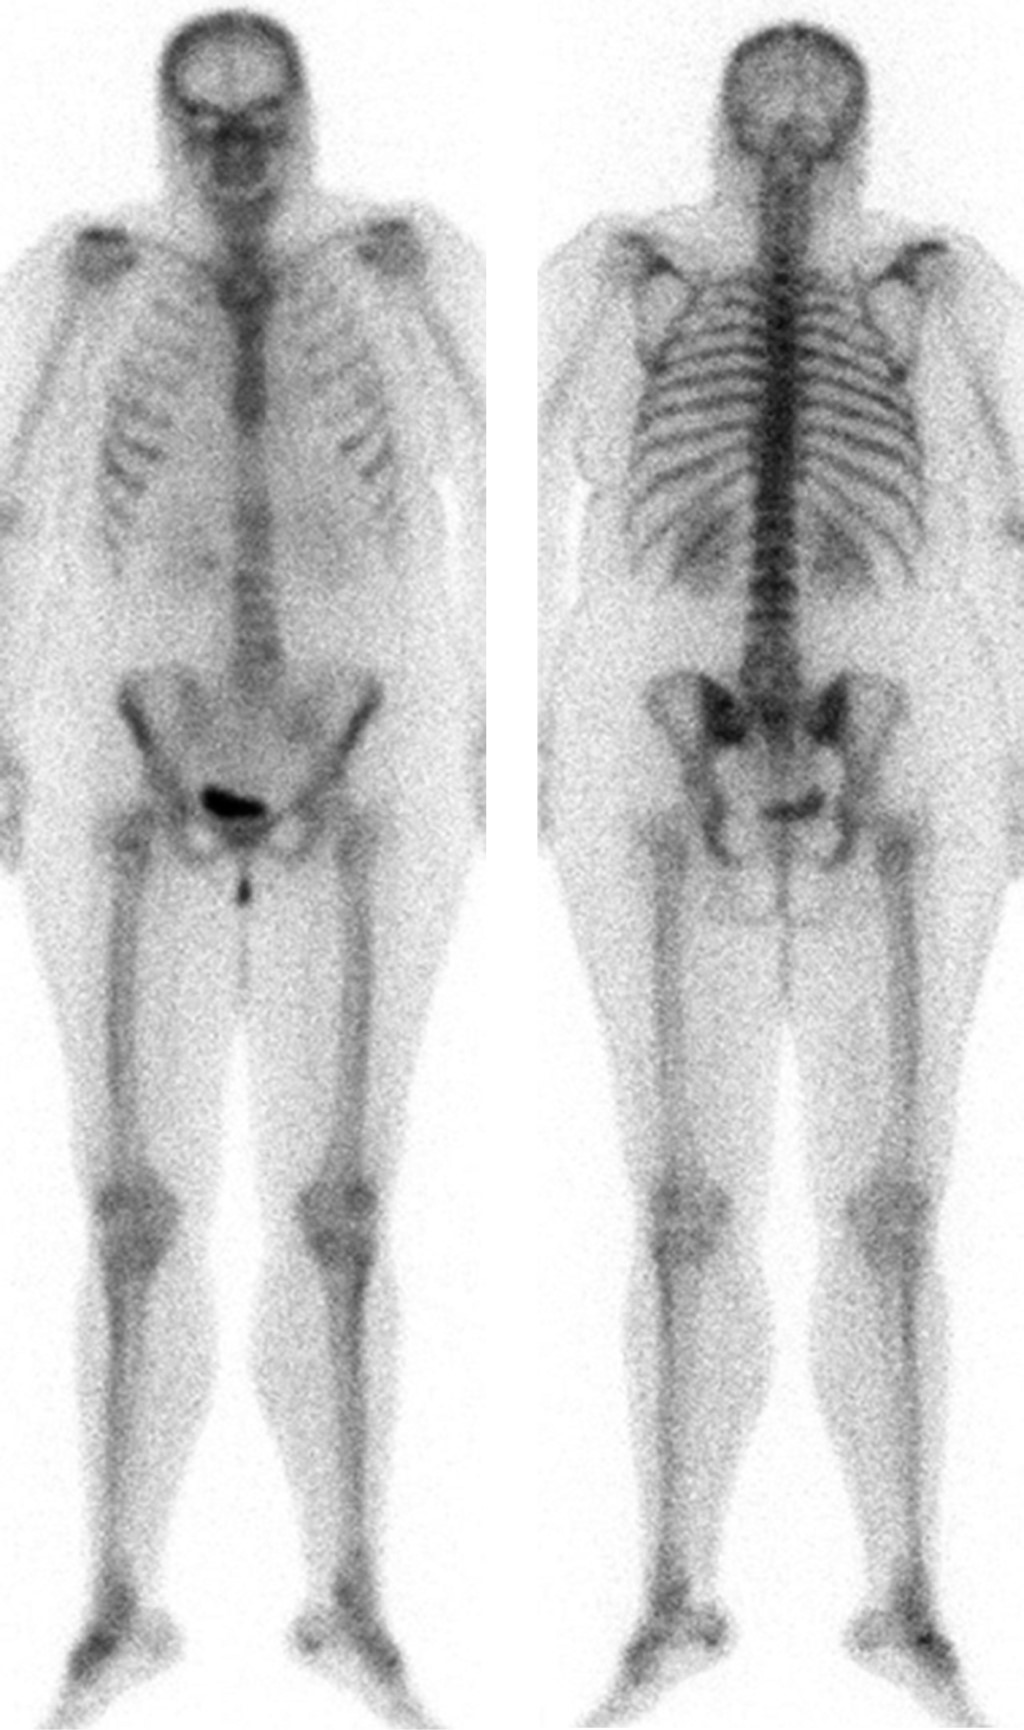

Liposclerosing myxofibroma of the proximal femur: diagnostic and therapeutic controversies. Apropos of 3 clinical cases

Introduction: The bone liposclerosing myxofibrous tumour (LSMFT) is a rare benign fibro-osseous tumor with characteristic clinical-radiological features, although its diagnosis and treatment are controversial. Material and methods: We present three patients, two women and one man, with a mean age of 46 years, diagnosed with LSMFT. The findings of the complementary imaging tests and the treatment performed are presented: observation in two patients and curettage, and the third patient was treated with curettage, grafting and surgical fixation. Results: The first two patients, after 10 and three years of follow-up, respectively, maintain the same symptoms and no progression of the lesion. Conclusions: The diagnosis of LSMFT can be assumed by clinical and imaging data without biopsy. In the absence of signs that suggest malignancy, observation is justified, limiting the surgical indication to symptomatic cases and/or those with risk of pathological fracture.

Figure 1